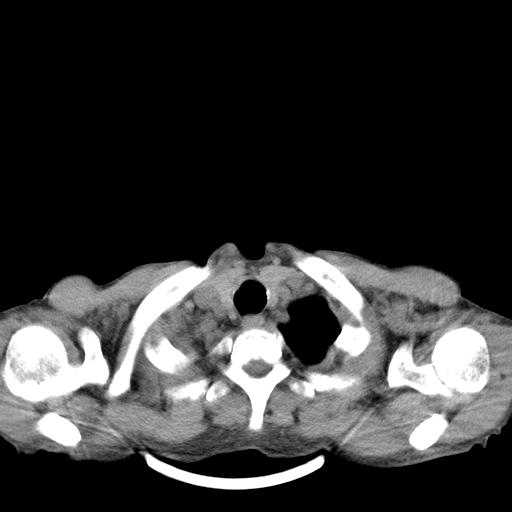

男性 75  咳嗽 一周前发热最高达39

右肺继发型tb并右侧tb性胸腔炎,右侧胸腔大量积液并右下肺膨胀不全,慢支肺气肿、多发肺大泡。建议抽胸水实验室检查并复查排除恶性在占位。

右上肺继发型肺结核,右胸腔中等量积液。

左上肺大泡。

结核的基础上有纵隔淋巴结肿大,右侧有胸水,但右侧纵隔反而窄,说明有肺有不张。

1)右肺继发型肺结核。2)左肺胸膜下多发性肺大泡。3)右侧胸腔积液。